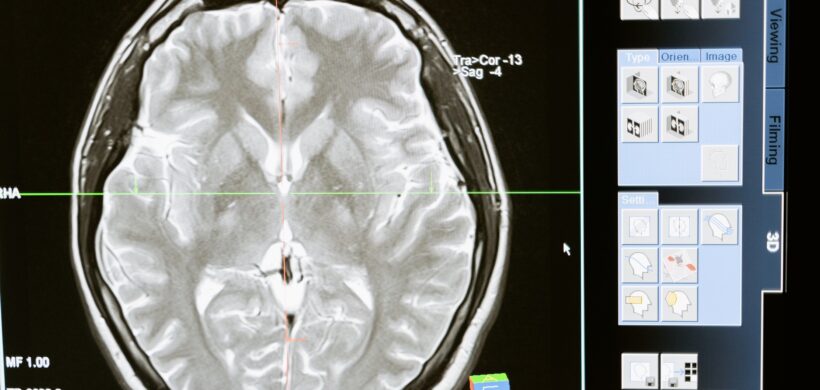

La atrofia cortical posterior (ACP) es una afección progresiva de índole neurológica que genera alteraciones visuales complejas con preservación del estado cognitivo hasta estadios avanzados de la enfermedad. Existe evidencia de compromiso degenerativo de los lóbulos occipitales, parietales y/o temporales posteriores. La ACP es catalogada como una de las variantes atípicas de la Enfermedad de Alzheimer siendo nombrada casi exclusivamente como su “variante visual”. La edad promedio de diagnóstico de esta afección es entre los 50 a los 60 años.

En este artículo se hará referencia exclusivamente al compromiso visual de los pacientes con ACP, y a los hallazgos en la evaluación oftalmológica.